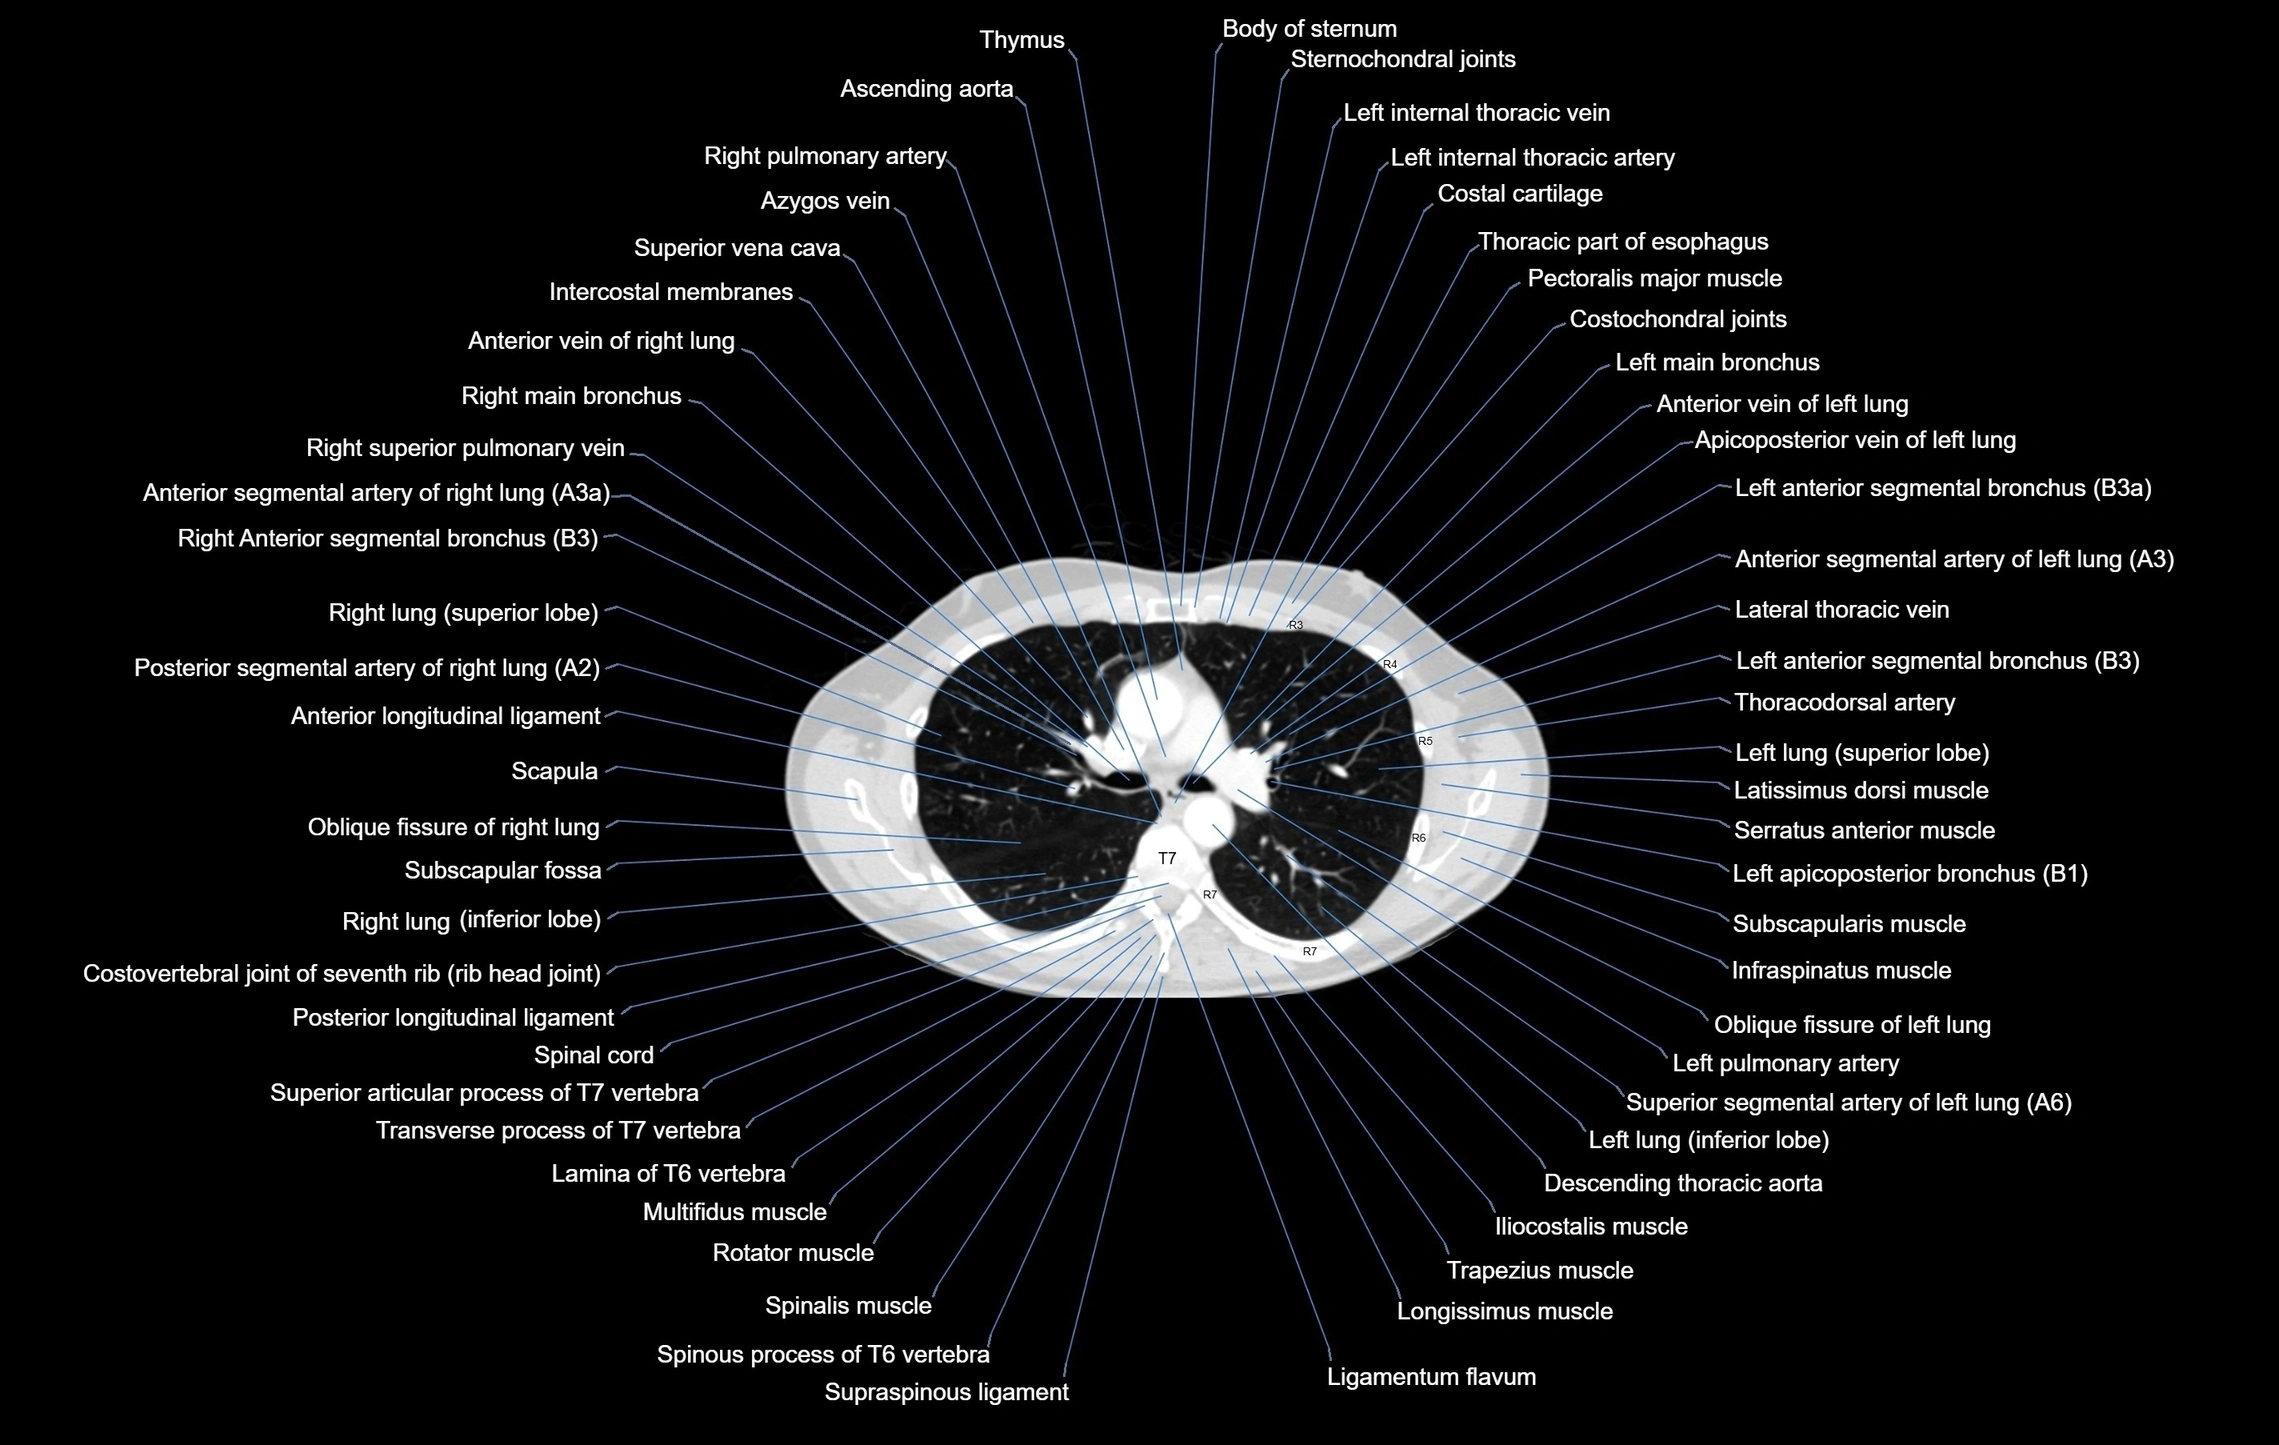

- Ascending aorta

- Azygos vein

- Descending thoracic aorta

- Infraspinatus muscle

- Latissimus dorsi muscle

- Multifidus muscles

- Right main bronchus

- Right pulmonary artery

- Subscapularis muscle

- Trapezius muscle